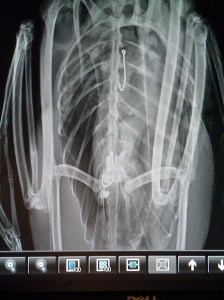

Initial x-rays revealed not just one hook, but two hooks similar to a rig for walleye fishing. One of the hooks had already made its way deep into the proventriculus. The proventriculus is one part of two parts of a bird’s stomach. It has very acidic pH which softens food to make it easier for the bird to digest. There was also a spot on the x-ray which could’ve been a lead sinker or a rock. If it was indeed a lead sinker, the possibility of lead poisoning was highly likely.